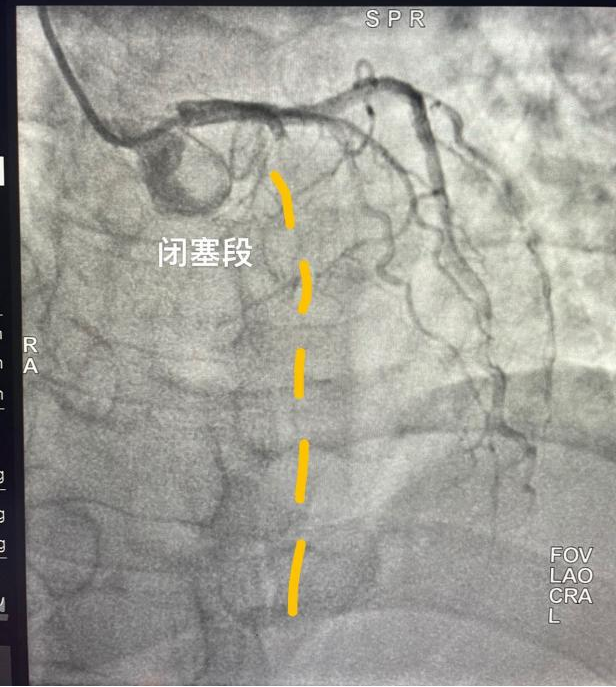

進入導管室後,立即開始消毒、鋪單、局麻、穿刺等操作(zuò),僅6分(fēn)鍾即完成冠脈造影,11分(fēn)鍾即恢複閉塞段血流,術中患者再次出現(xiàn)室顫,搶救成功,45分(fēn)鍾完成全部手術,術後患者生(shēng)命體(tǐ)征平穩,入重症監護室治療,2天後轉入普通病房(fáng),病情好(hǎo)(hǎo)轉後出院。經1個(gè)月(yuè)(yuè)随訪患者心髒功能(néng)等各項指标恢複良好(hǎo)(hǎo)。